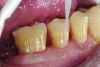

Fig 2 and Fig 3. In Case 1, occlusal (Fig 2) and buccal (Fig 3) preoperative views of defective Class I and Class V amalgam restorations on mandibular first permanent molar.